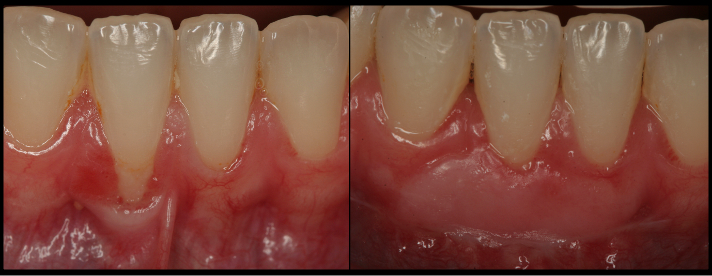

• Cover receding roots and improve the esthetics and restorative outcomes.

Learn How to Do Frenectomies & Simple Grafts

Learn how to execute effective frenectomies and how you can perform simple soft tissue grafts in your practice.